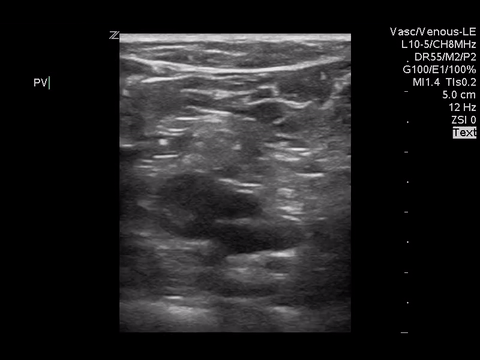

Right lower extremity

In each of these images it appears the vein fully collapses with compression. We can conclude that there is likely no DVT present within the limitations of the 2-point compression scan (see discussion for further details)